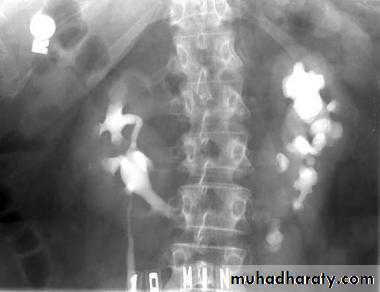

Bulb of follys cathter IVU with bilateral mild to moderate degree of HN

RT sided PUJ stenosis & obstruction with RT sided HN

Uretrocele (cobra head shape)distal both sided ureteric ends with dilated both ureters

Uretrocele